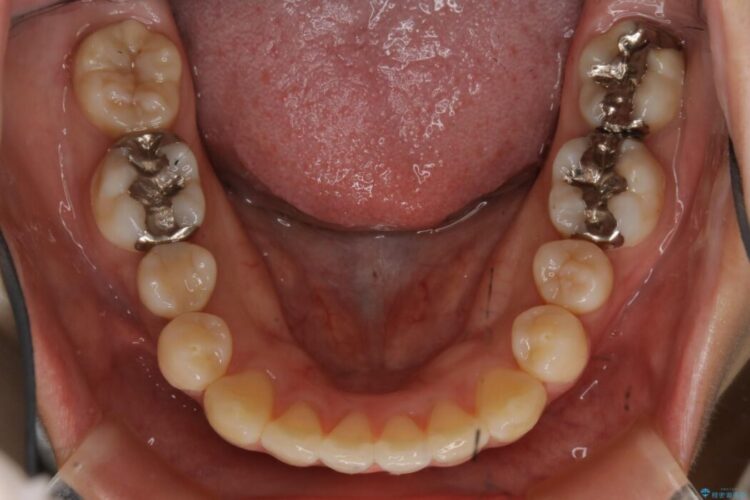

患者様からなおしたい内容をお聞きしたところ

・上下の歯のガタつき

・出っ歯感(口ゴボ)

・噛み合わせ

よって患者様ご希望の非抜歯かつマウスピースでの矯正を行うために、最大量の臼歯の遠心移動をして歯列全体を奥へ引っ込める計画をご提案しました。

非抜歯での矯正治療

マウスピースにマイクロインプラントという補助装置を併用することで抜歯をせずとも歯列を整えるスペースを確保することができます。奥歯から順に移動させていくので前歯に変化が出るまでには時間がかかってしまいますが、健康な歯を抜歯することなく理想的な歯並びを手に入れることができます。